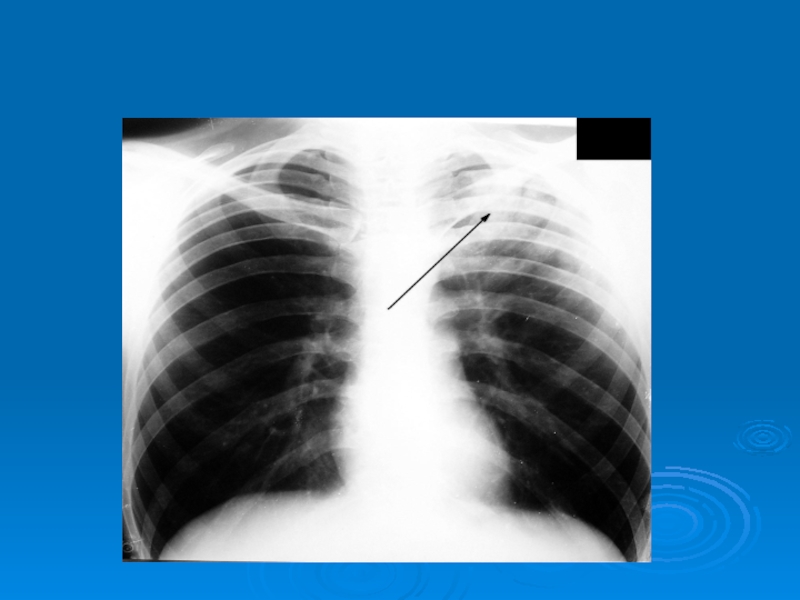

Слайд 35Затемнение части легочного поля (туберкулез в верхней доле левого легкого)

Затемнение части легочного поля (туберкулез в верхней доле левого легкого)